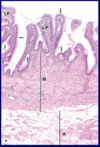

What are the tissue layers that make up the GIT and their specific roles.

Lumen

Mucosa (epithelium, lamina propria, muscularis propria)

Submucosa (LCT and submucosal (Meissner’s) nerve plexus)

Muscularis Externa (SKM, SM, myenteric (Auerbach’s) nerve plexus)

Serosa (Adventia)